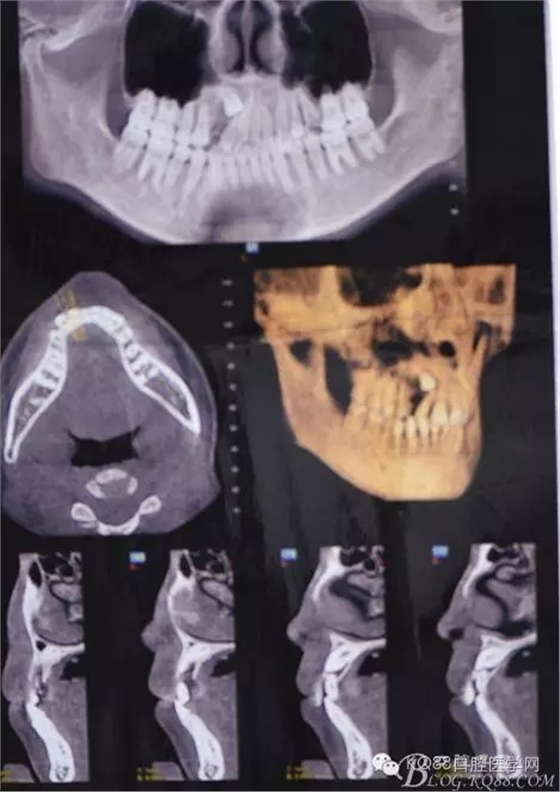

患者、女、高xx、17歲,主訴:外院轉診要求拔除埋伏牙。??茩z查:53殘根滯留、牙根斷面位于齦下,cbct檢查:13高位埋伏,牙冠壓迫12牙根的遠中面,牙根未見吸收,經(jīng)我院正畸科會診,建議拔除13、53,然后再正畸治療。患者同意治療方案,術前簽知情同意書。 拔牙過程: 圖1.術前的cbct檢查:13位于12遠中根尖區(qū),13牙根接近上頜竇、53牙根滯留。 圖2.口內(nèi)觀:53滯留、牙根斷面位于齦下,12牙冠唇傾。 圖3.合面觀:12畸形舌側窩、腭側沒有明顯隆起 圖4.首先拔除53,然后在23唇側區(qū)域的前庭溝處的黏膜做弧形切口 圖5. 翻瓣 圖6.去骨 圖7.暴露出13牙冠 圖8.高速渦輪機分牙、目的是盡量少去骨。 圖9. 從頸部截分13 圖10. 13牙冠頸部分牙情況 圖11.再把牙冠分成近中、遠中兩部分。 圖12.取出13牙冠 圖14.取出13牙根 圖15.取出的13的牙根 圖16.拔除13牙后形成的拔牙創(chuàng)。 圖17.拔除的13. 圖18.縫合